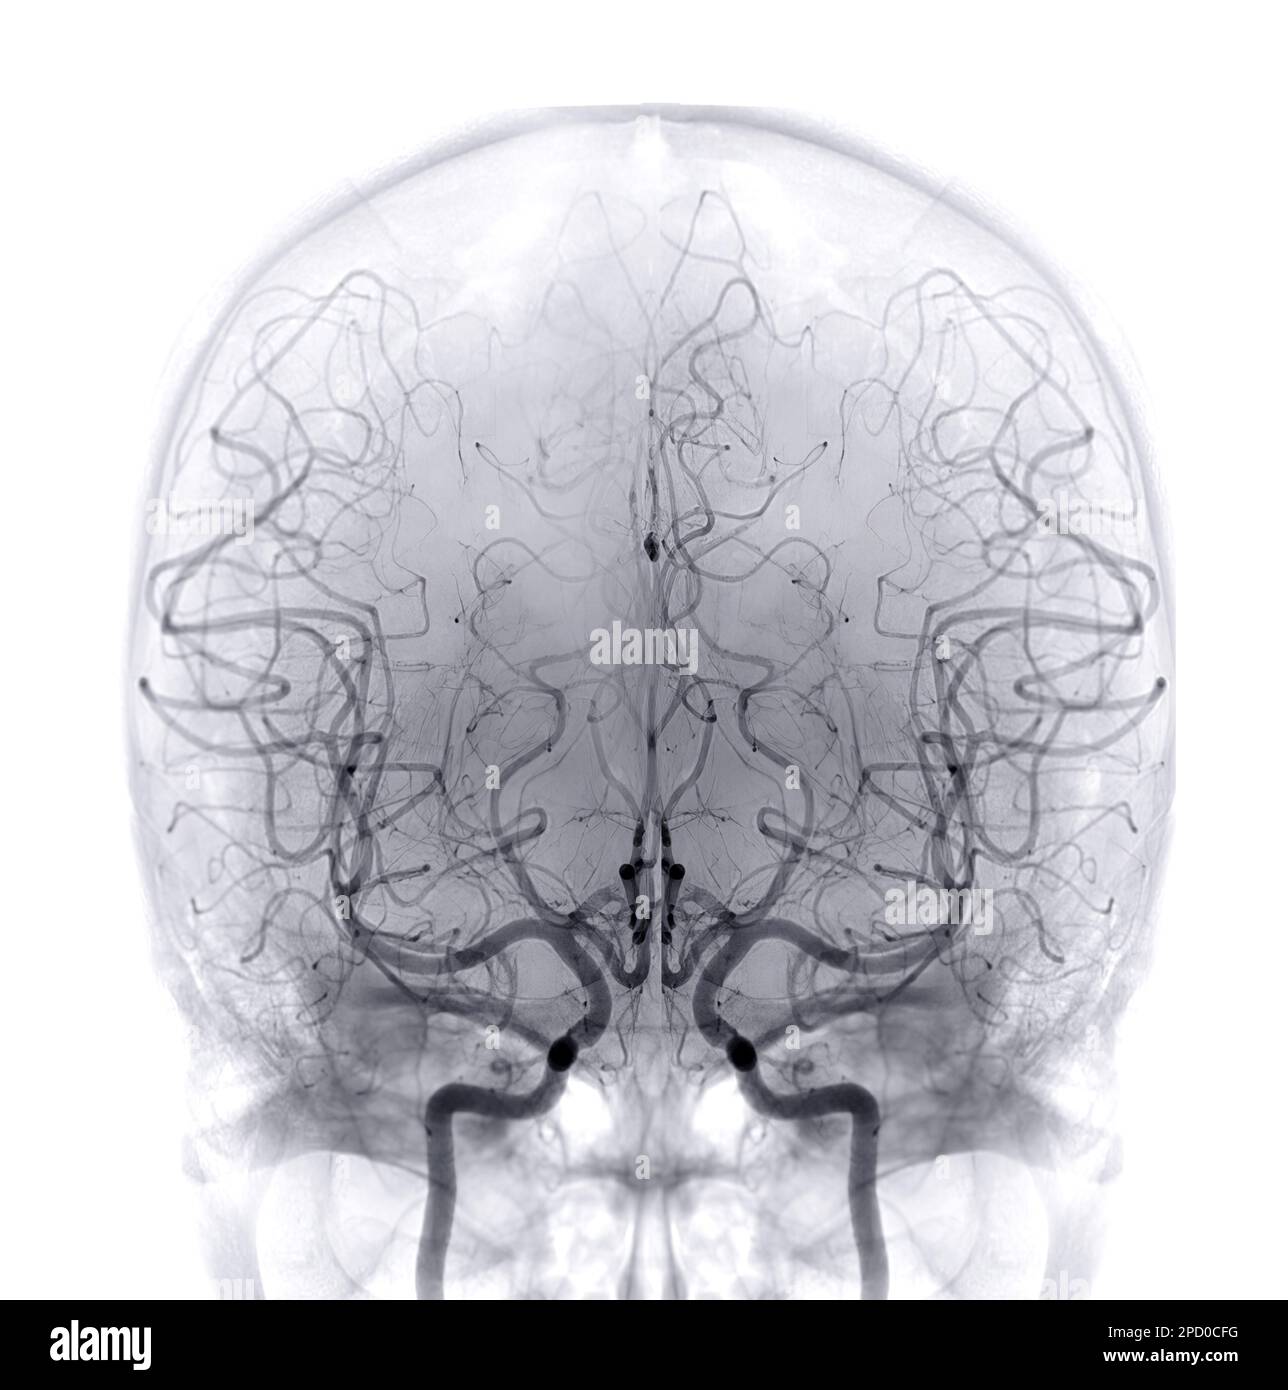

L'angiografia cerebrale è una forma di angiografia che fornisce immagini dei vasi sanguigni che si trovano all'interno e intorno al cervello, consentendo in tal modo l'individuazione di anomalie anatomiche, ad esempio malformazioni artero-venose, stenosi vascolari, aneurismi.

Tipicamente un catetere viene inserito in una grande arteria (in genere l'arteria femorale a livello dell’inguine) e fatto scorrere attraverso il sistema circolatorio in via retrograda fino all'arco aortico e fino ad ottenere la successiva incannulazione selettiva dell'arteria carotide e/o dell'arteria vertebrale. Una volta raggiunto questo sito l'esaminatore procede ad iniettare un mezzo di contrasto iodato. Una prima serie di radiografie viene presa mentre il mezzo di contrasto si diffonde attraverso il sistema arterioso del cervello. Successivamente si scatta una seconda serie di radiografie quando il mezzo di contrasto raggiunge il sistema venoso. L'acquisizione di queste immagini è resa possibile grazie all'utilizzo di un apposito apparecchio a raggi X chiamato angiografo digitale Prima degli anni '70 la tipica tecnica prevedeva la cateterizzazione tramite un ago, direttamente nell'arteria carotidea, al fine di bypassare l'anatomia tortuosa dell'arco aortico e del tronco brachiocefalico. Questa modalità di approccio è stata sostituita dal metodo corrente di infilare un catetere da una diversa arteria, a causa delle frequenti complicazioni causate da un trauma di un'arteria del collo (in particolare temibili gli ematomi del collo con possibile compromissione delle vie aeree). Le attuali apparecchiature angiografiche tridimensionali grazie all’utilizzo di sofisticati software permettono di ottenere immagini ad alta risoluzione estremamente chiare e dettagliate.

L’esame rappresenta il “gold standard” per la diagnostica delle malformazioni vascolari del cervello ed in particolare per la diagnosi degli aneurismi e delle malformazioni artero-venose (MAV).